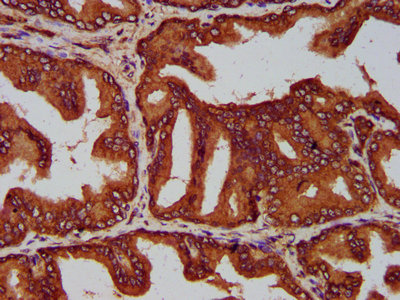

IHC image of CSB-PA769777LA01HU diluted at 1:200 and staining in paraffin-embedded human prostate tissue performed on a Leica BondTM system. After dewaxing and hydration, antigen retrieval was mediated by high pressure in a citrate buffer (pH 6.0). Section was blocked with 10% normal goat serum 30min at RT. Then primary antibody (1% BSA) was incubated at 4°C overnight. The primary is detected by a biotinylated secondary antibody and visualized using an HRP conjugated SP system.

IHC image of CSB-PA769777LA01HU diluted at 1:200 and staining in paraffin-embedded human prostate cancer performed on a Leica BondTM system. After dewaxing and hydration, antigen retrieval was mediated by high pressure in a citrate buffer (pH 6.0). Section was blocked with 10% normal goat serum 30min at RT. Then primary antibody (1% BSA) was incubated at 4°C overnight. The primary is detected by a biotinylated secondary antibody and visualized using an HRP conjugated SP system.